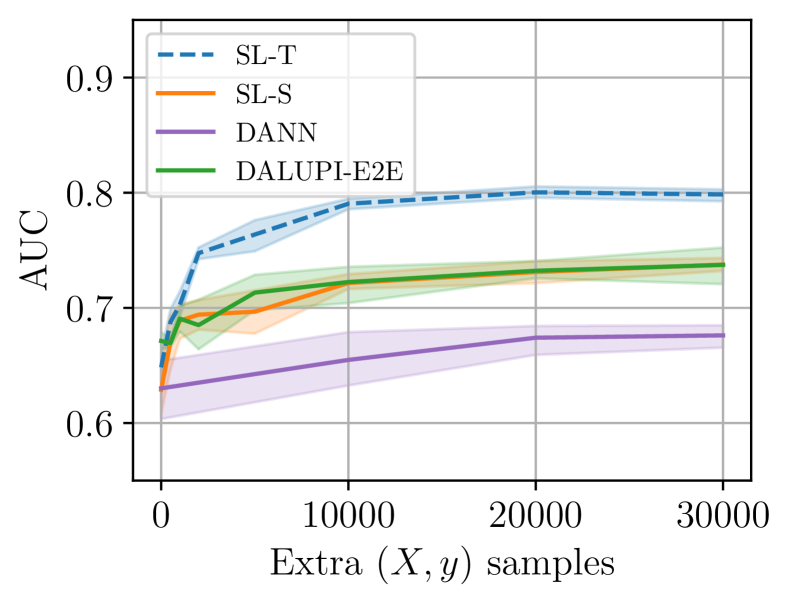

5.3 X-ray classification

As a real-world experiment, we study detection of pathologies in chest X-ray images. We use the ChestX-ray8 dataset Wang et al. (2017) as source domain and the CheXpert dataset Irvin et al. (2019) as target domain. As privileged information, we use bounding boxes localizing each pathology. For the CheXpert dataset, only pixel-level segmentations of pathologies are available, and we create bounding boxes that tightly enclose the segmentations. It is not obvious that the pixels within such a bounding box are sufficient for classifying the pathology, and we suspect that we may violate the assumptions of Proposition 1 in this experiment. However, as we find below, DALUPI-E2E improves empirical performance compared to baselines for small training sets, thereby demonstrating increased sample efficiency.

We consider the three pathologies that exist in both datasets and for which there are annotated findings: atelectasis (ATL; collapsed lung), cardiomegaly (CM; enlarged heart), and pleural effusion (PE; water around the lung). There are 457 and 118 annotated images in the source and target domain, respectively. We train DALUPI-E2E and DANN using all these images. SL-S is trained with the 457 source images and SL-T with the 118 target images as well as 339 labeled but non-annotated target images. Neither SL-S, SL-T nor DANN use any privileged information. In the annotated images, there are 180/146/153 and 75/66/64 examples of ATL/CM/PE in each domain respectively. Validation and test sets are sampled from the non-annotated images.

In Table 2 we present the per-class AUCs in the target domain. DALUPI-E2E outperforms all baseline models, including the target oracle, in detecting CM. For ATL and PE, it performs similarly to the other feasible models. That SL-T is better at predicting PE is not surprising given that this pathology is most prevalent in the target domain. In Figure 5(a), we show a single-finding image from the target test set with ground-truth label CM. The predicted bounding box of DALUPI-E2E with the highest probability is added to the image. DALUPI-E2E identifies the region of interest and makes a correct classification. The bottom panel shows the saliency map for the ground truth class for SL-S. We see that the gradients are mostly constant, indicating that the model is uncertain. In Figure 5(b), we show AUC for CM for DALUPI-E2E, SL-S, and SL-T trained with additional examples without bounding box annotations. We see that SL-S catches up to the performance of DALUPI-E2E when a large amount of labeled examples are provided. These results indicate that identifiability is not the primary obstacle for adaptation, and that PI improves sample efficiency.